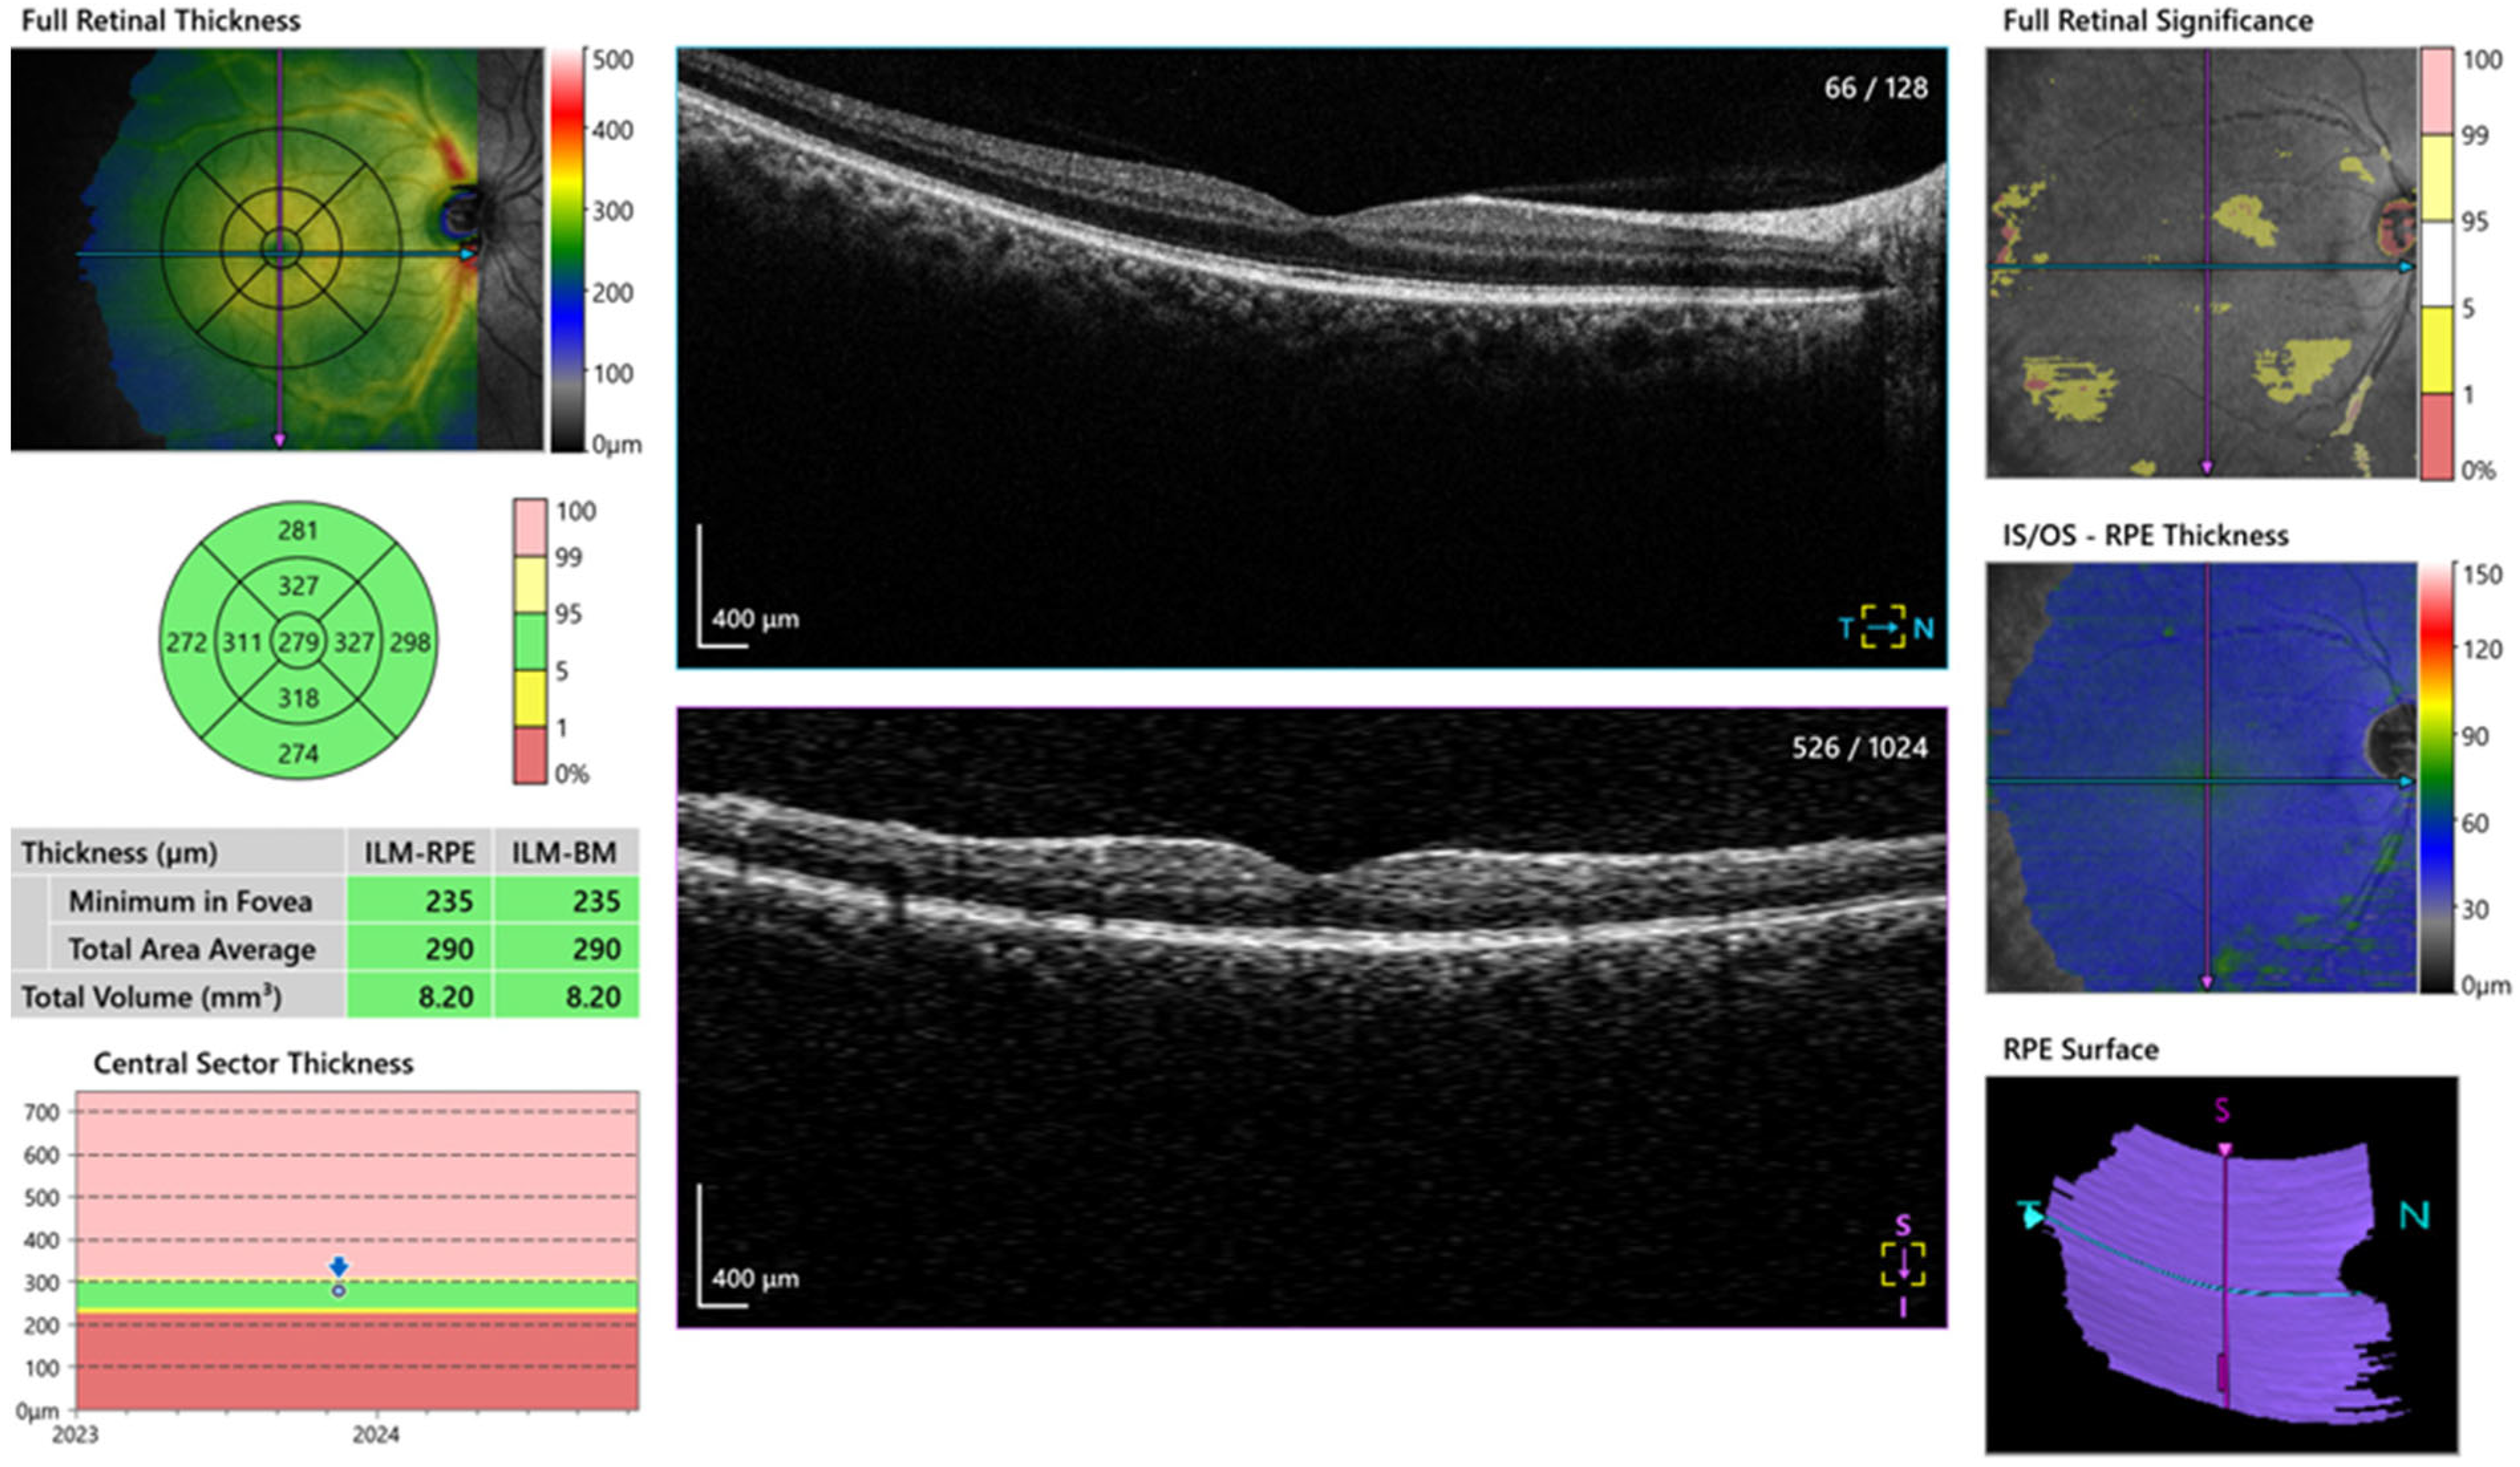

| Macula | 268.4 ± 19.9 | 276.3 ± 21.7 | 0.149 * |

| Central macula, Mean ± SD | 120.0 ± 14.3 | 129.6 ± 15.8 | 0.016 * |

| RNFL superior, Mean ± SD | 121.6 ± 14.7 | 135.9 ± 19.8 | 0.002 * |

| RNFL inferior, Mean ± SD | 73.2 ± 8.4 | 74.7 ± 11.8 | 0.566 * |

| RNFL temporal, Mean ± SD | 83.0 ± 9.8 | 88.2 ± 12.0 | 0.075 * |

| RNFL nasal, Mean ± SD | 378.0 ± 59.0 | 411.6 ± 60.7 | 0.033 * |

| Central choroid, Mean ± SD | 315.3 ± 55.3 | 356.8 ± 50.6 | 0.004 * |

| Nasal choroid, Mean ± SD | 350.7 ± 51.0 | 379.9 ± 55.4 | 0.038 * |